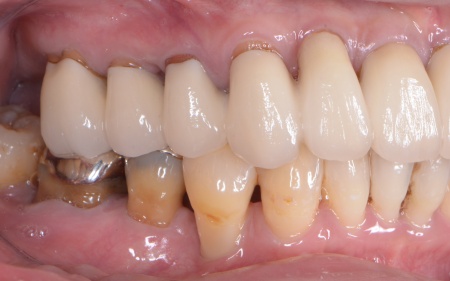

| 相談内容 | 「右下の奥歯が噛むと痛い」とご相談いただきました。 |

| カウンセリング | 拝見したところ、右下の奥歯(第1大臼歯)に歯根破折が確認でき、これが痛みの原因だと考えられます。 歯根破折をそのまま放置すると、歯を支える骨の吸収が進んだり周囲の歯茎が炎症を起こしたりする可能性があります。 そこで、レントゲン検査などで詳しく確認した結果、ひびは根の深い部分まで達しており、残念ながら歯を温存することは困難です。 また、その手前の小臼歯は、過去の治療で装着した詰め物の下で虫歯が再発する二次カリエスが見つかりました。このまま放置すると虫歯がさらに広がる可能性があります。 以上のことから、右下の大臼歯は抜歯後に欠損を補う治療、手前の小臼歯は虫歯の再治療が必要と診断しました。 |